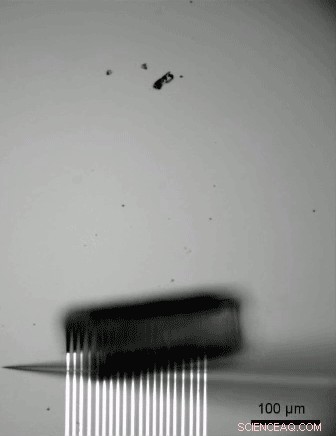

Highly flexible 3D biosensor array unrolling with a glass capillary. Credit: Carnegie Mellon University College of Engineering

"Mechanics analysis of the roll-up process enables us to precisely control the shape of the sensors to ensure conforming contact between the sensors and the cardiac tissue," says NTU Professor Jimmy Hsia. "The technique also automatically adjusts the level of the delicate 'touch' between the sensors and the tissue such that high quality electric signals are measured without changing in the physiological conditions of the tissue due to external pressure."

The organ-on-e-chip starts out similarly. The researchers pin an array of sensors made of either metallic electrodes or graphene sensors to the chip's surface, then etch off a bottom layer of germanium, which is known as the "sacrificial layer." Once this sacrificial layer is removed, the biosensor array is released from its hold and rolls up from the surface in a barrel shaped structure.